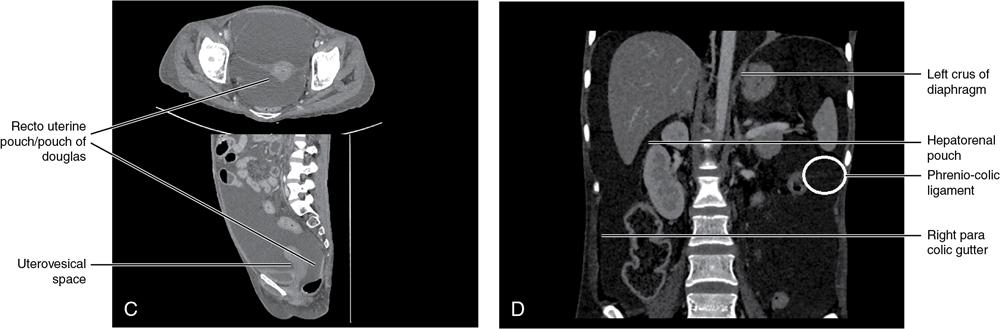

CROSS SECTIONAL ANATOMY OF ABDOMEN Satya Jha NORMAL ANATOMY OF ABDOMEN AND PELVIS Amandeep Singh The two major surfaces: The anterior and posterior layers of the coronary ligament converge on bare area (not covered by peritoneum). Its right and left margins form the right and left triangular ligaments. The right triangular ligament extends toward the diaphragm and separates right subphrenic space from right subhepatic space. The left triangular ligament gives tracts extending to the diaphragm and falciform ligament and does not compartmentalize the left subphrenic space. Ligamentum teres or the obliterated umblical vein is contained in falciform ligament which attaches the liver to anterior abdominal wall. The main portal vein, the proper hepatic artery and the common bile duct are contained within investing peritoneal folds of hepatoduodenal ligament at the porta hepatis (Fig. 7.2.2.1). Liver is divided into eight segments which are functionally independent and have their own vascular supply and biliary drainage. Arterial circulation: The branches of the hepatic artery accompanying the portal veins. Hepatic venous system: The right, middle, and left hepatic veins draining into IVC (Figs. 7.2.2.2 and 7.2.2.3). The gallbladder is a blind pear-shaped muscular membranous sac which is an embryologic derivative of the foregut, is a pouch lying along the undersurface of the liver. The gallbladder fossa is located in the plane of the interlobar fissure, which lies between the right and left hepatic lobes. Its major function is to store and concentrate bile which is produced by the liver. It measures approximately 4 cm in diameter when it is normally distended. Gallbladder is a smaller tubular structure in contracted state. The normal gallbladder wall thickness ranges from 1 to 3 mm. The gallbladder is divided into the fundus, body and neck. Infundibulum is present in the region of neck of the gallbladder, which is called the Hartmann pouch, where gallstones are usually impacted. Intrahepatic biliary radicles (IHBRs) scattered throughout the liver get confluent towards the hilum. They unite to form the right and left main hepatic ducts which further unite to form common hepatic duct (CHD) at the hilum. Common bile duct is formed by the union of cystic duct with common hepatic duct. The main pancreatic duct is joined with the common bile duct to form the ampulla of Vater at the major duodenal papilla (Figs. 7.2.2.4 and 7.2.2.5). Pancreas is located in anterior pararenal space of retroperitoneum anterior to perirenal (Gerota’s) fascia and posterior to parietal peritoneum. It is divided into head, uncinate process, neck, body and tail from right to left. Pancreas lies anterior to portal vein, which marks the point of transition between the body and neck. The region between head of pancreas and second and third parts of duodenum is known as the pancreatic groove. In postnephrectomy cases or with agenesis of kidney or ectopic kidney, pancreas moves posteriorly to partially fill in the empty renal fossa; its soft tissue density should not be mistaken for recurrent tumour. It is located in the pancreatic groove and is bounded superiorly by the duodenal bulb, laterally by second portion of duodenum, inferiorly by third portion of duodenum, medially by superior mesenteric vein and anterior to inferior vena cava. It is a wedge or wedge shaped lying posterior to superior mesenteric artery and vein. It is an imaginary junction between the head and body and lies directly over the junction of the splenic vein and superior mesenteric vein. It is located posterior to the lesser sac and anterior to the aorta, left adrenal gland, left kidney, and renal vessels and runs obliquely upward to the left of the superior mesenteric vessels. It is situated median to the colonic flexure and anterior to the left kidney. It is located in close proximity to the splenic hilum without a notable relation with the body of pancreas. It is seen anterior to the left kidney and median to the colonic flexure. The distal part of the tail passes between the peritoneal layers of the splenorenal ligament (Fig. 7.2.2.6 and 7.2.2.7).